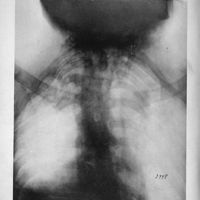

0011 - Page 229 - Radioscopie er radiographie (Pl. XXXI)

0007 - Page 227 - Colonne vertébrale (Pl. XXX)